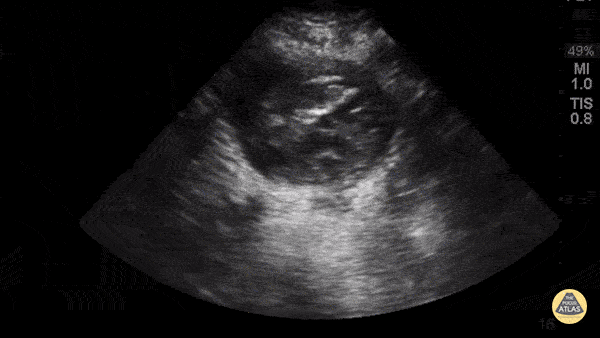

Aorta - Aorta Posterior Wall Rupture

63yoM witnessed collapsed. Arrived VSA with PEA rhythm. A fast look abdominal aorta POCUS showed a large abdominal aortic aneurysm with internal thrombus and rupture through the posterior wall. Note the AAA is measured from echogenic outer wall to outer wall, not the hypoechoic internal lumen that is seen pulsating. The patient was resuscitated aggressively with blood and initially survived operative repair. Unfortunately he died in the ICU several days later from multiorgan failure. Dr. Joey Newbigging